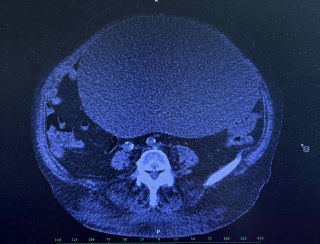

Хочу поділитися цікавим випадком за сьогодні 😍 Синдром Хілайдіті [ гепатодіафрагмальна інтерпозиція ] — це рідкісний с...